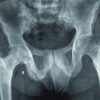

Atlantoaxial fusion was performed 8 weeks after her initial presentation. The atlas and axis were fixed with bilateral transarticular screws after reducing the atlas, followed by an autologous iliac bone graft (Fig. 3a, b).